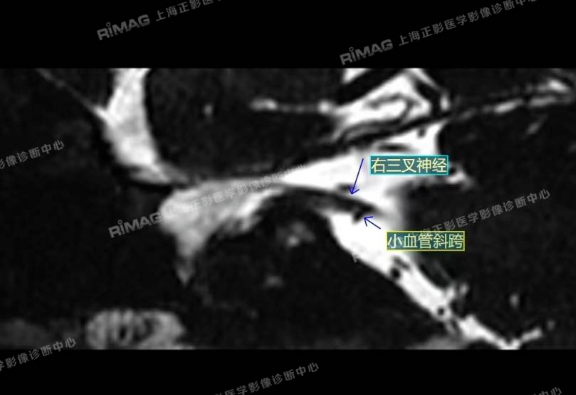

影像表现:右侧三叉神经根部外下方见小血管斜跨,与三叉神经分界不清;左侧未见明显异常(对照)。

MRTA:磁共振体层成像脑血管显影术,可清楚显示三叉神经与周围血管空间关系,为术前筛选、术中探查责任血管,提高手术疗效等提供了可靠的影像学依据。